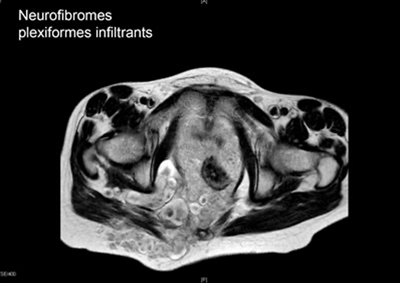

- Signe d’appel cutané évoquant un neurofibrome plexiforme infiltrant

.png.aspx?width=400&height=283)